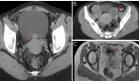

La radiografía de tórax confirmó la presencia de dextrocardia sin signos de consolidación pulmonar. La tomografía computarizada de alta resolución demostró bronquiectasias difusas, posición anómala del hígado en hemiabdomen izquierdo y signos de bronquiolitis infecciosa.

Los estudios de senos paranasales revelaron cambios compatibles con sinusitis crónica, completando así los criterios diagnósticos del síndrome.

El diagnóstico del SK requiere una evaluación integral que combine la clínica con estudios complementarios. La tomografía computarizada de alta resolución (HRCT) torácica es fundamental para demostrar las bronquiectasias y confirmar las anomalías de lateralidad, según relatan los autores del estudio (Iván Ruíz-Ángel, et al).